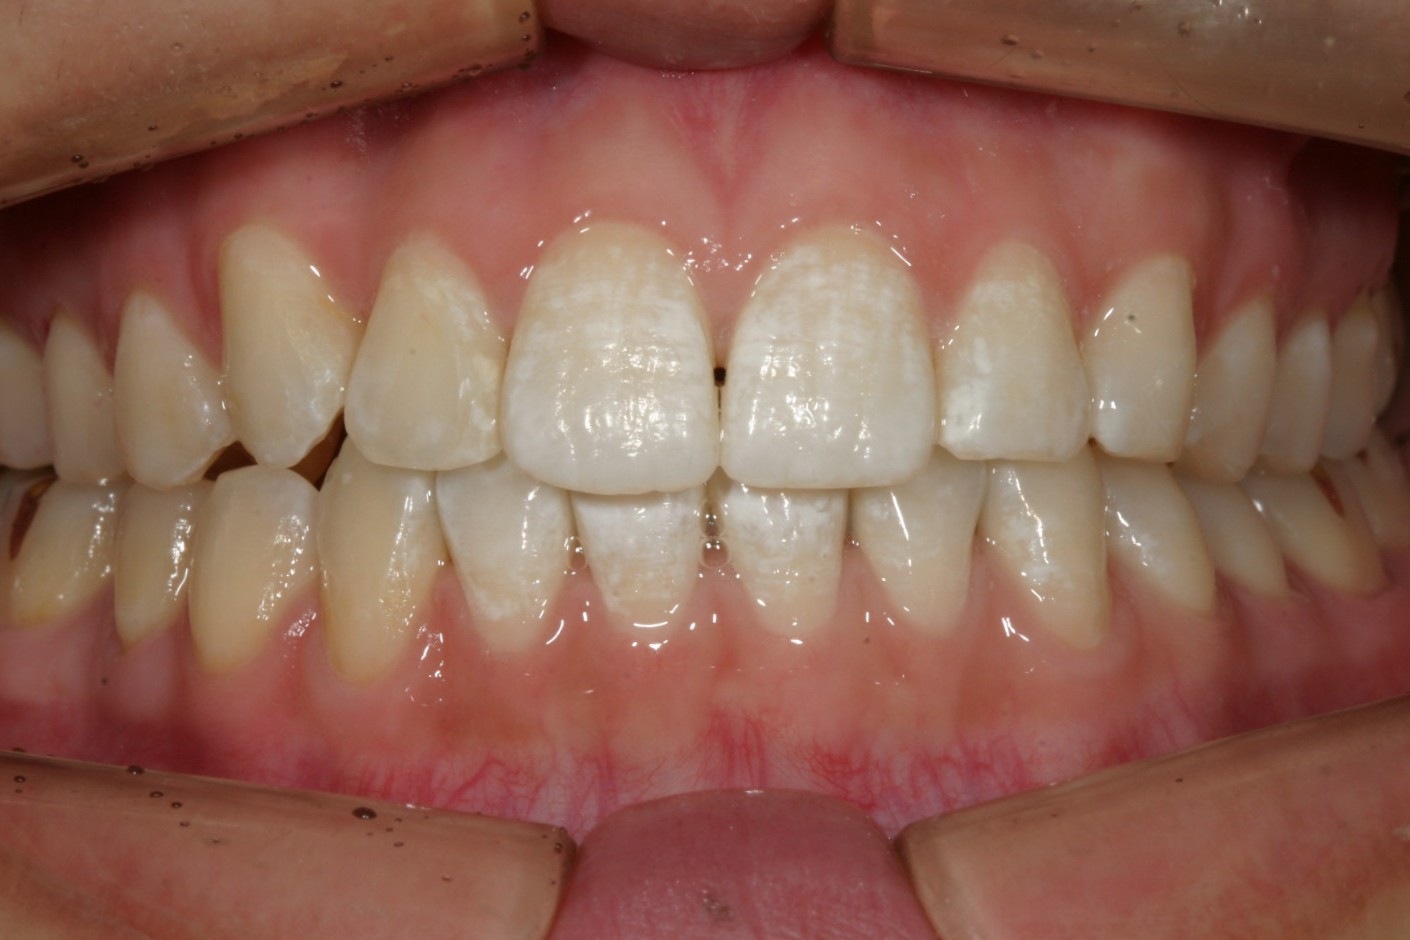

綺麗に並びましたね〜

下顎も改善しました。

噛み合わせもバッチリです。